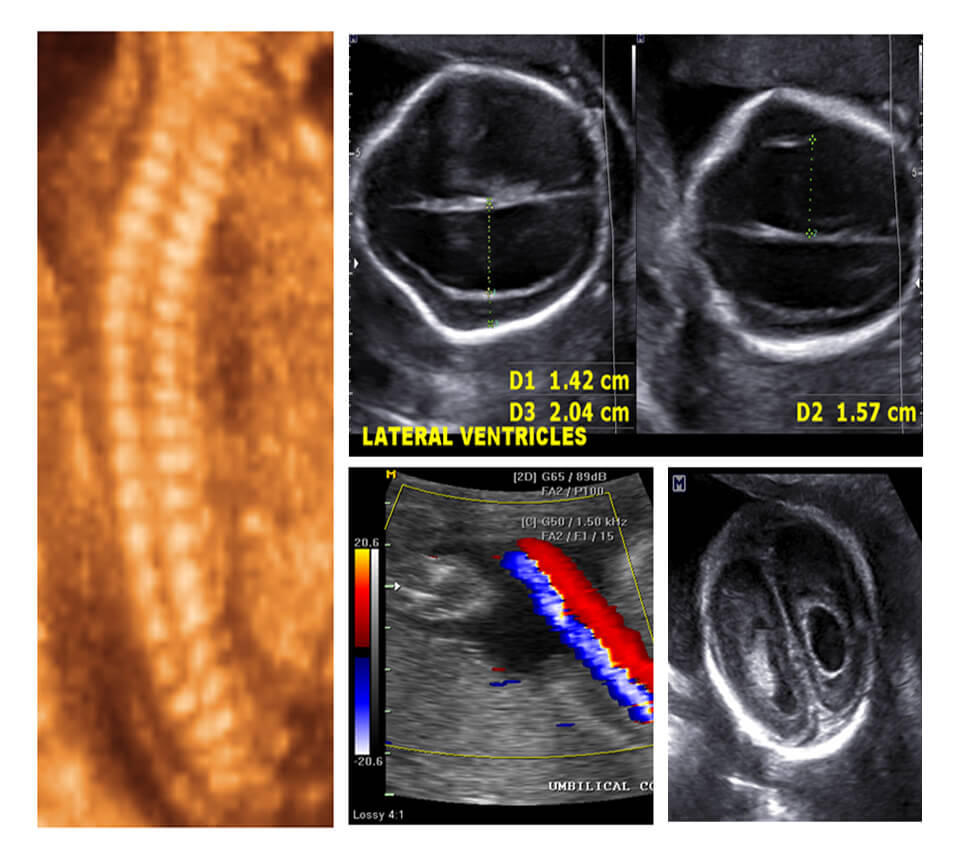

Week 3 SECOND TRIMESTER NORMAL & FETAL SPINE

Week 4 FETAL CRANIUM

Session 6 UMBILICAL/MCA/DV/AORTIC ISTHMUS + ASSIGNMENT SUBMISSION

Session 7 UMBILICAL/MCA/DV/AORTIC ISTHMUS + ASSIGNMENT SUBMISSION

Session 8 COLOR DOPPLER SECOND TRIMESTER ANOMALIES AND CARDIAC EVALUATION

Session 9 FETAL ANEMIA/TWINS/ACCRETA